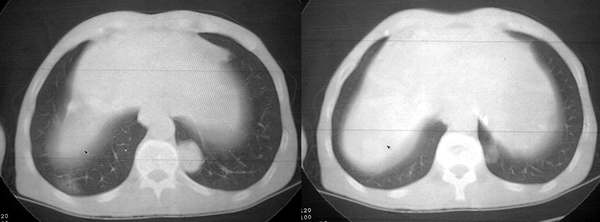

双肺内及胸壁旁见有多发软组织实性阴影和空洞,实性病变多见有脐凹切迹,贴近胸膜的见有胸膜凹陷征;空洞的壁多为厚薄不均,形态不规则,纵隔内见有较多肿大淋巴结,诊断为双肺内转移性病变。

右肺门软组织块影,右主支气管及中间段支气管管壁明显增厚,两肺内多发结节及大小不等的类圆形薄壁空洞,纵隔内多发肿大的淋巴结;

考虑:1.右中央型肺癌伴两肺广泛性转移及纵隔转移。

双肺空洞型转移性灶

肺癌双肺转移。以前见过像这样治疗后空洞增多的。